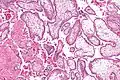

Histopathology of a chorionic villus, in a tubal pregnancy.

The bulk of the villi consist of connective tissues that contain blood vessels. Most of the cells in the connective tissue core of the villi are fibroblasts. Macrophages known as Hofbauer cells are also present.